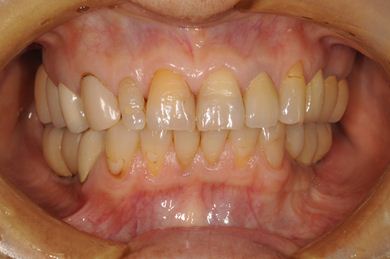

インプラントの症例写真 IMPLANT

骨再生インプラント治療+セラミック治療

| 治療内容 | インプラント6本(ソケットリフト)、ハイブリッドセラミック14本(ハイブリッドセラミック用土台5本、遊離歯肉移植術 | ||||||||||||||||||||||||||||||||

| 総治療費 | 2,751,445円 | ||||||||||||||||||||||||||||||||

| 治療期間 | 2年3ヶ月 |